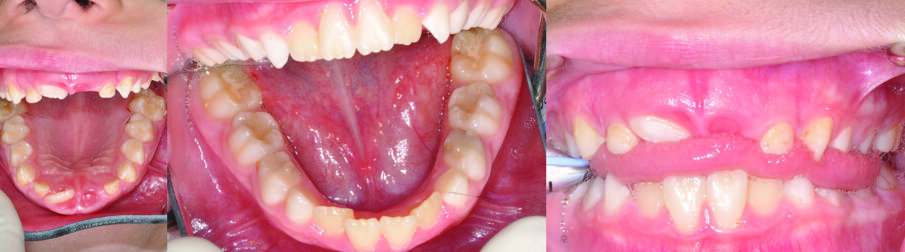

An eight and half year-old girl (LT) attended the paediatric dentistry department of Hamdan Bin Mohammed College of Dental Medicine (HBMCDM) in Dubai Healthcare City for an opinion. The patient’s mother was concerned about the delayed eruption of an upper front tooth (21) that was affecting her child’s appearance (Figs. 1 a, b & c). LT was medically fit and healthy with no history of previous dental trauma. She was in the mixed dentition stage. Tooth 11 had erupted 4 months ago in cross bite but 21 had not erupted yet. Its eruption was much delayed (usually erupts at 7 ½ years of age). Looking back at previous x-rays, a DPT was taken a year ago and it was noticed that an important feature was missed. Retrospectively, the presence of a supernumerary tooth ($) in the area of 21 and congenital missing 47 was confirmed (Fig. 2). Two new x-rays, namely upper intra oral periapicals and the parallax technique (distal shift) showed a supernumerary tooth (conical and inverted) in a palatal position (Figs. 3 a & b). LT also had dental caries of her primary teeth (Figs. 4 a & b), had a pronounced gag reflex and was dentally anxious.

Figs. 1 (a, b & c). An 8 ½ year old girl presented with delayed eruption of 21 and a palpable palatal swelling. Lower teeth were carious; see bitewings in Figure 4